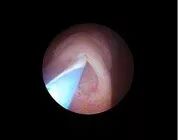

图 1 输尿管开口

输尿管镜经尿道进入膀胱,沿输尿管间嵴找到输尿管开口(图 1),靠近开口后置入导丝,挑起导丝,拉长输尿管开口(图 2),在持续灌注下输尿管口会张开,输尿管镜即可进入输尿管。